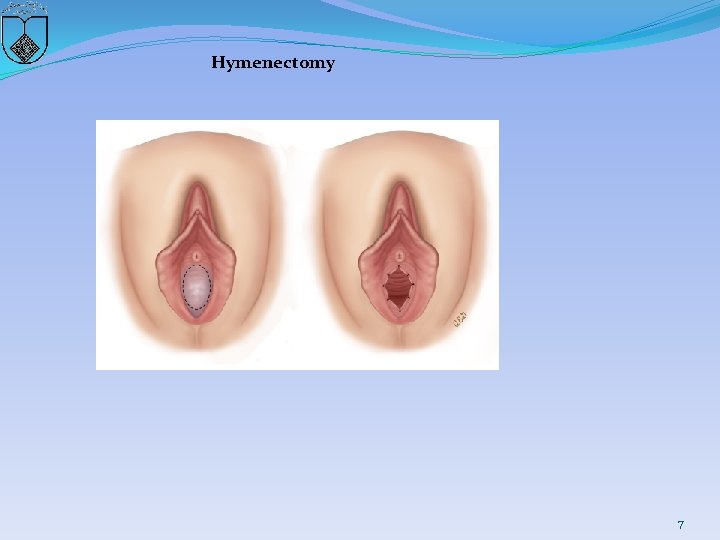

Hymenectomy 7